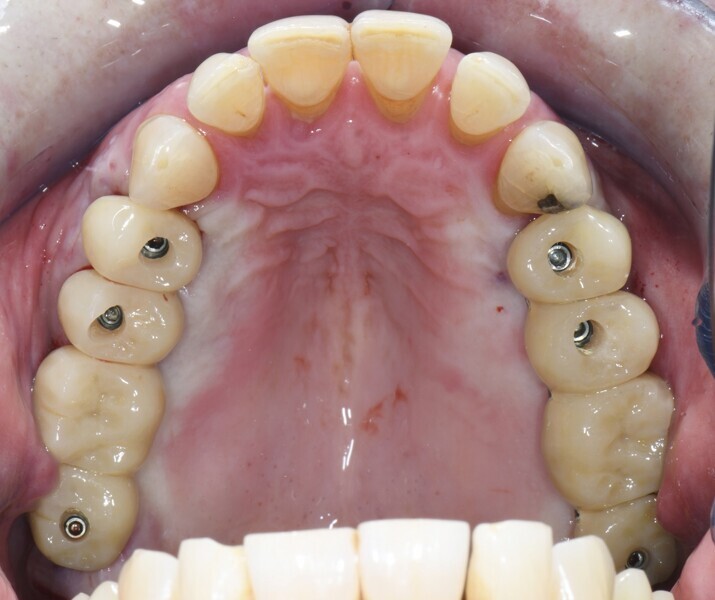

PrimeTaper EV implants (Dentsply Sirona) were placed in the maxillary premolar and molar positions (Fig. 2). MultiBase Abutments EV (Dentsply Sirona) were positioned and temporary screw-retained bridges loaded immediately (Figs. 3 & 4). To ensure that the implant positions were correct, a postoperative radiograph was performed (Fig. 5).

After a healing period of six months (Fig. 6), an intra-oral scan was performed at abutment level together with a scan of the existing temporary bridges in relation to the opposing arch (Figs. 7–11).